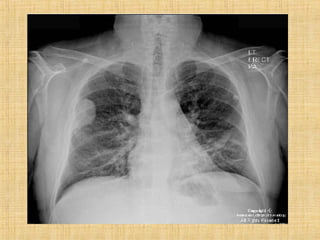

As principais informações do documento são: 1. Discute os padrões de doença pulmonar causados por metástases, incluindo nódulos, espessamento intersticial e obstrução das vias aéreas. 2. A prevalência de metástases pulmonares varia de 30-55% dependendo do tumor primário, e são mais comuns em pacientes acima de 50 anos. 3. Os achados clínicos mais comuns são dispneia, hemoptise e febre, enquanto exames de escarro ou lavado brô